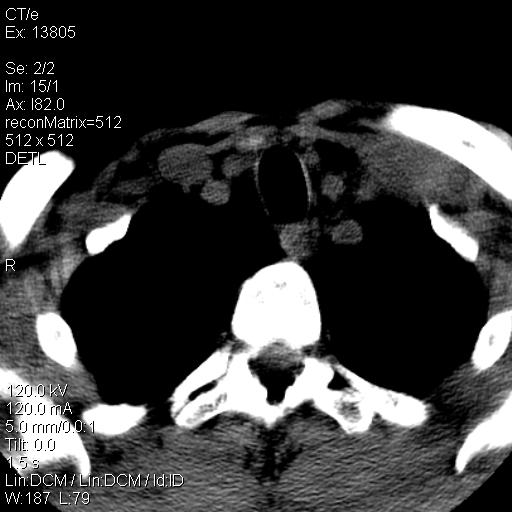

上腹部疼痛一月,呕吐10天,发现左侧颈部包快10天 胸部cr片未见明显异常。

左侧胸锁乳突肌下方、颈血管旁低密度肿块影,肿块密度尚均匀,边缘大部分清楚,邻近组织稍受压移位。考虑颈部神经鞘瘤可能性大。

颈部及腹膜后淋巴瘤可能性大